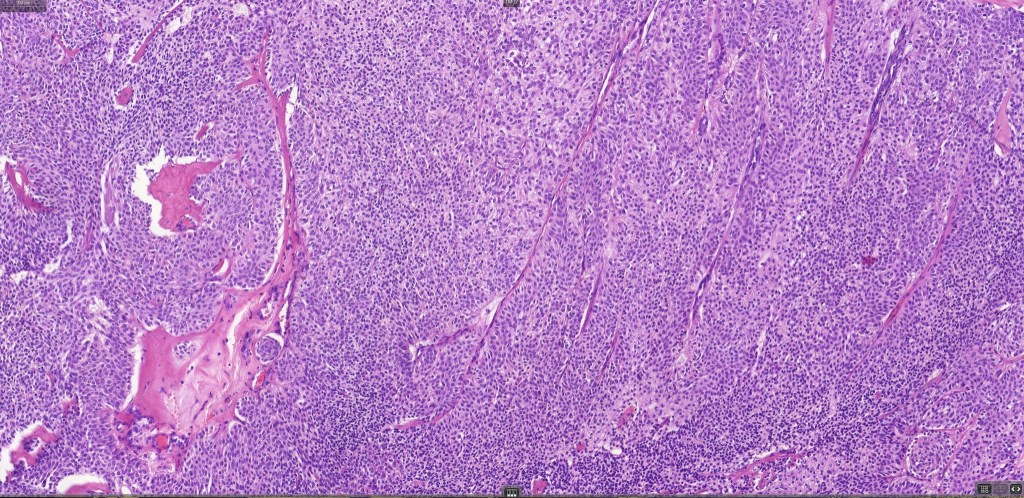

Histological features

•Variably derived from the acrosyringium, the dermal duct or both

•Dermal duct tumor comprises dermal nodules composed of poroid cells showing ductal differentiation & intracytoplasmic lumina with variable cyst formation

•In poroma, a dermal-centric tumor is associated with epidermal origin/continuity & is composed of small cells with vesical nuclei.

•Desmosomes often prominent

•No peripheral palisading or retraction artifact

•Generally few mitoses but occasionally can be conspicuous. In the absence of other features of porocarcinoma, this should not be taken as necessarily implying maligant potential unless other worrying features sre also present (see case below)

•No pleomorphism or abnormal mitoses